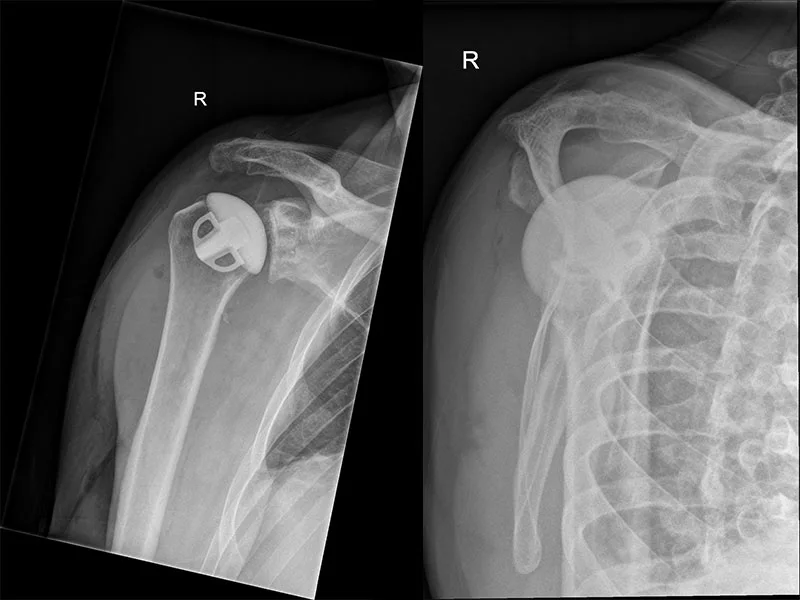

Die anatomische Schulter-Prothese

Ist die Rotatorenmanschette der Schulter intakt, kann eine anatomische Prothese eingesetzt werden. Hierbei werden nur der Kopf des Oberarmes und die Pfanne mit kleinen Implantaten ersetzt. Die Funktion dieser Prothesen ist sehr gut. Eine Lebensdauer nach Implantation kann 15-20 Jahre betragen.